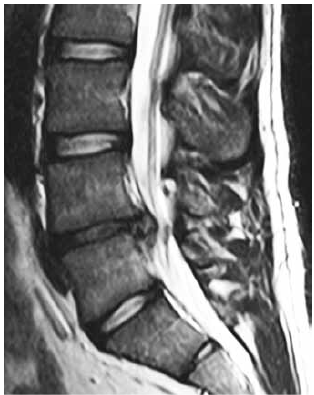

Observe a imagem a seguir.

Uma hérnia de disco lombar em segmento L4-L5 que ocorre em paciente jovem, com quadro agudo de forte ciática para MID, apresentando boa marcha após uso de AINES, mas paresia na extensão do hálux D e na dorsiflexão do pé, tem como melhor conduta: